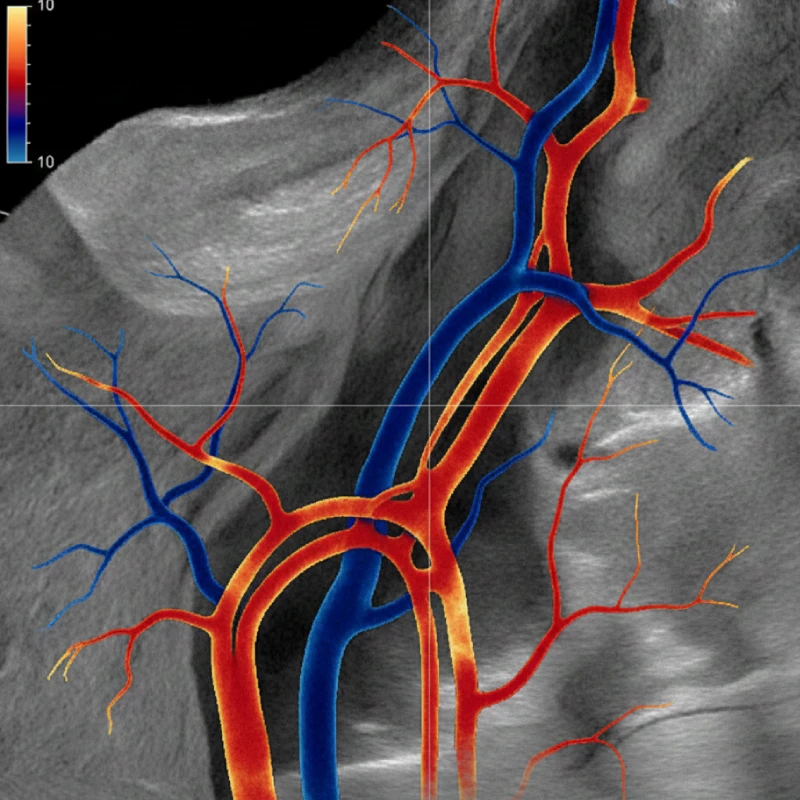

پ) داپلر رنگی (Color Doppler)

در این روش جریان خون به صورت رنگی روی مانیتور نمایش داده میشود. داپلر رنگی برای نمایش کلی الگوی جریان خون و یافتن ناهنجاریهای اولیه بسیار مفید است.

عملکرد داپلر بر پایه فرستادن امواج صوتی به داخل بدن است. دستگاه امواج را به سمت رگها ارسال میکند و پس از برخورد امواج با گلبولهای قرمز در حال حرکت، بازتاب مییابند. دستگاه با تحلیل تغییر فرکانس بازتابشده، اطلاعاتی مانند سرعت جریان خون، جهت حرکت خون و الگوی جریان را محاسبه کرده و نتیجه را بر روی صفحه نشان میدهد. نرمافزار دستگاه دادهها را به شکل نمودار یا تصویر رنگی تبدیل میکند که پزشک از آن برای تشخیص دقیقتر استفاده میکند.